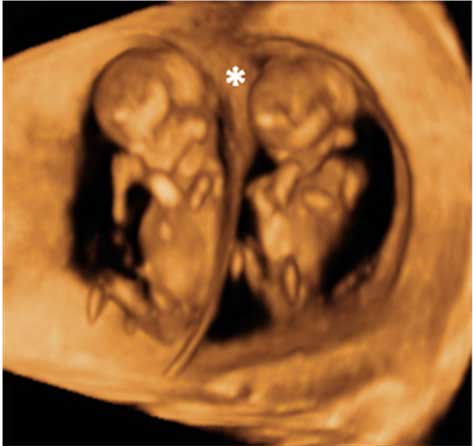

¿Qué anomalías fetales pueden detectarse en la semana 12?

Hay un grupo de anomalías mayores ya detectables en esta semana de embarazo. Entre ellas figuran: ventriculomegalia (dilatación de los ventrículos cerebrales), holoprosencefalia (faltan la diferenciación de los hemisferios cerebrales), anencefalia/exencefalia (faltan los huesos del cráneo y acaba desapareciendo el cerebro), alteraciones faciales groseras, cardiopatías estructurales importantes, onfalocele (exteriorización de vísceras abdominales a través del ombligo), agenesia renal (ausencia de riñón), megavejiga (vejiga excesivamente grande) y alteraciones groseras de las extremidades.